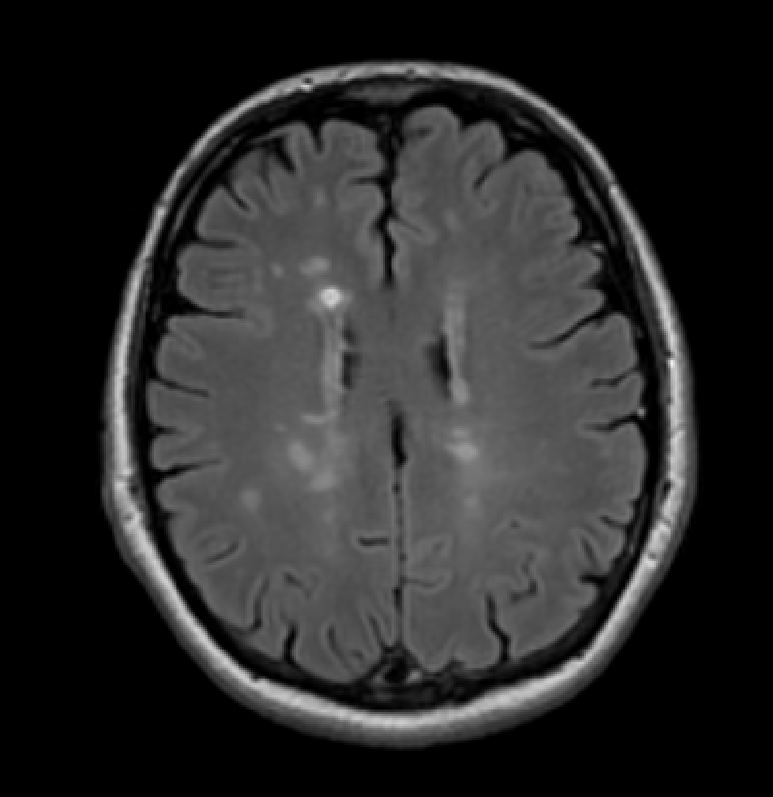

Информация о диссеминированном рассеянном энцефаломиелите